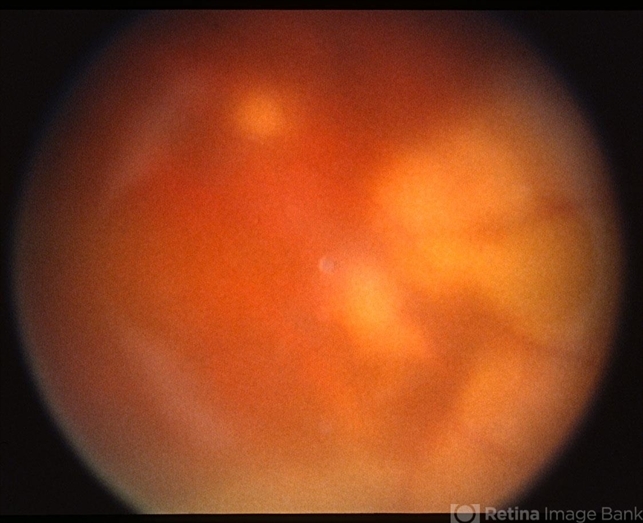

- ocular toxoplasmosis, vitritis

- Color fundus photograph showing vitreous haze and confluent peripheral retinal whitening consistent with active ocular toxoplasmosis.